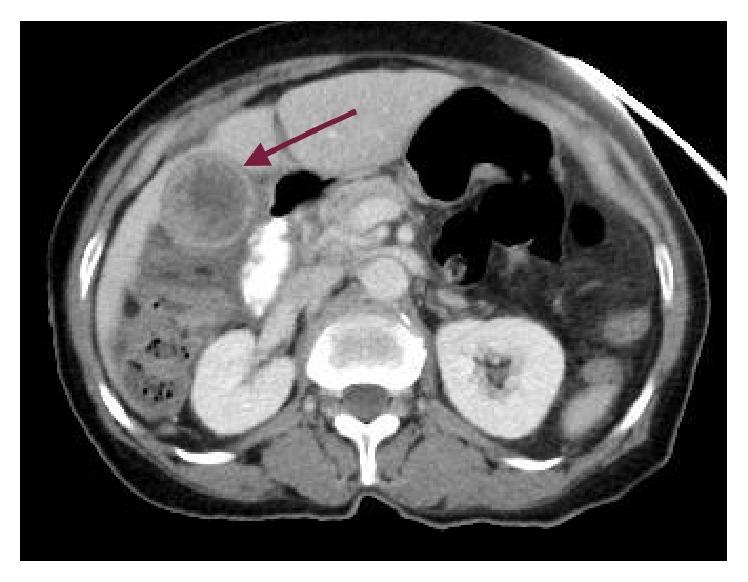

Primary pure squamous cell carcinoma (SCC) of the gallbladder is an exceptionally rare type of tumor that comprises only 1% of all gallbladder cancer. SCC of the gallbladder portends a worse prognosis than the more common adenocarcinoma variant because of its aggressive invasion to local structures and because it is often diagnosed at an advanced stage. Owing to its rarity, diagnosis and management can be challenging. Herein, we present the case of a 75-year-old female complaining of abdominal pain, nausea, and vomiting. Computed tomography and ultrasonography results of the abdomen were consistent with acute cholecystitis and cholelithiasis. Histologic evaluation of the resected mass revealed a malignant tumor with prominent keratinization, confirming the diagnosis of an invasive primary pure SCC of the gallbladder. Microscopic examination showed direct infiltration to the liver, duodenum, and stomach. This case report describes the hospital course of a patient with SCC of the gallbladder and suggests that gallbladder cancer should be considered as part of the differential diagnosis in elderly patients presenting with acute cholecystitis. In addition, this article will review existing literature to examine the utility of different diagnostic techniques and treatment modalities available in the management of gallbladder cancer.

原发性纯胆囊鳞状细胞癌(SCC)是一种极为罕见的肿瘤类型,仅占所有胆囊癌的1%。胆囊SCC的预后比更常见的腺癌变体更差,这是因为它对局部结构具有侵袭性,且常常在晚期才被诊断出来。由于其罕见性,诊断和治疗颇具挑战性。在此,我们报告一例75岁女性患者,其主诉腹痛、恶心和呕吐。腹部计算机断层扫描和超声检查结果与急性胆囊炎和胆结石相符。对切除肿块的组织学评估显示为一个具有显著角化的恶性肿瘤,确诊为侵袭性原发性纯胆囊SCC。显微镜检查显示肿瘤直接浸润至肝脏、十二指肠和胃。本病例报告描述了一名胆囊SCC患者的住院过程,并提示在患有急性胆囊炎的老年患者中,应将胆囊癌纳入鉴别诊断范围。此外,本文将回顾现有文献,以探讨不同诊断技术和治疗方式在胆囊癌管理中的效用。